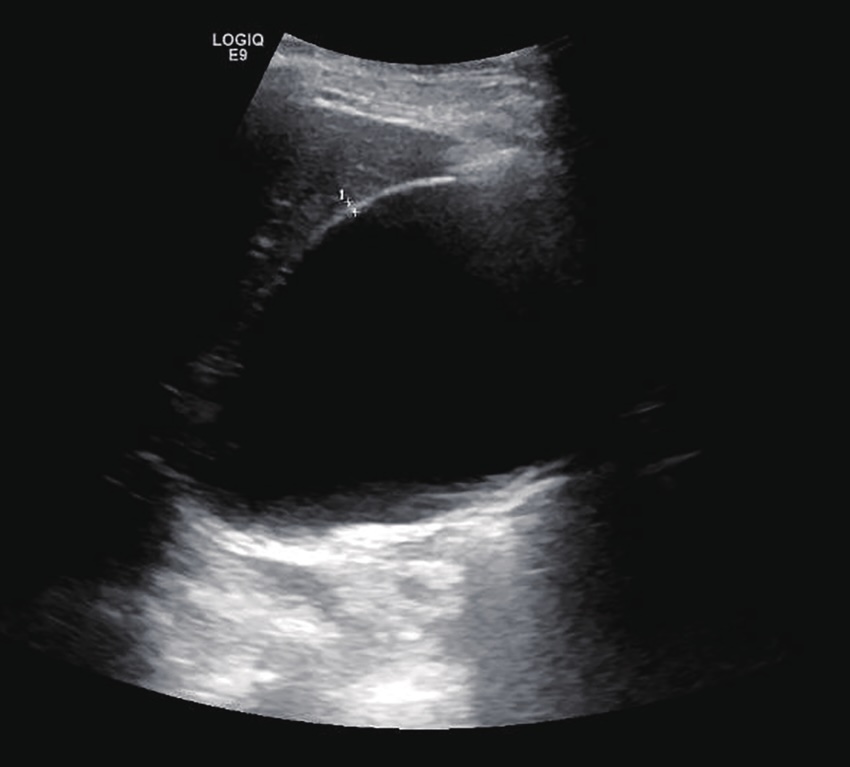

Ультразвуковое исследование проводится при подозрении на водянку жёлчного пузыря с целью выявления прямых анатомических признаков перерастяжения органа, застоя содержимого и нарушения пассажа по пузырному протоку. Исследование выполняется в В-режиме трансабдоминально натощак для оптимизации визуализации стенки и содержимого пузыря.

Ультразвуковое исследование выявляет следующие анатомические признаки водянки жёлчного пузыря:

Продольный размер жёлчного пузыря превышает 100 мм, поперечный — более 40 мм.

Форма органа грушевидная с чёткими, растянутыми контурами без признаков деформации.

Толщина стенки уменьшена, составляет менее 2 мм, стенка визуализируется как тонкая и равномерная.

Полость пузыря заполнена анэхогенным однородным содержимым без признаков перемешивания.

Отсутствие акустических теней и эхосигналов, свидетельствующих о газах или хлопьях.

Признаки компрессии прилегающих тканей или органов при значительном увеличении пузыря.

Гиперэхогенные включения в проекции шейки или пузырного протока с дистальной акустической тенью, диаметром менее 3 мм.